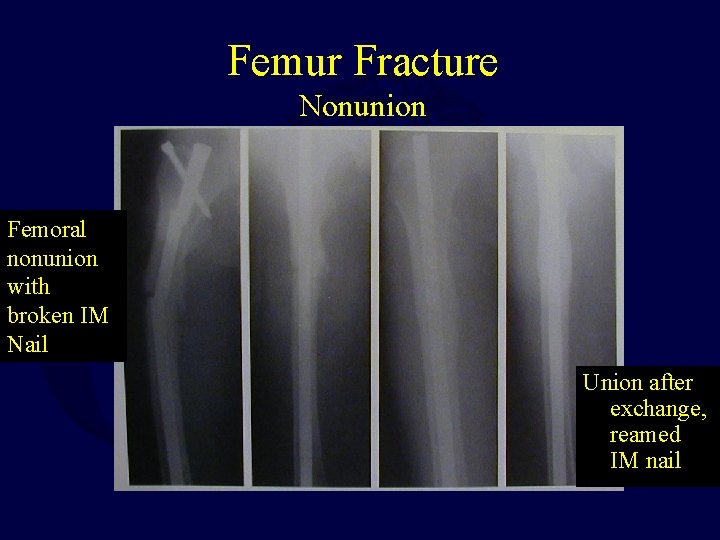

Femur Fracture Nonunion Femoral nonunion with broken IM Nail Union after exchange, reamed IM nail